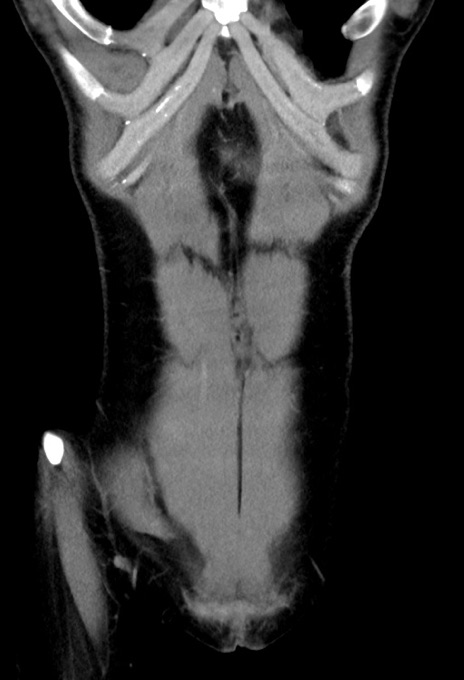

症例17(冠状断像)

【症例】20歳代女性

【主訴】嘔吐、下腹部痛

【現病歴】昨日夕食後に嘔吐し下腹部痛が出現。本日になっても嘔吐持続し改善しないため来院。

【身体所見】意識清明、BT 37.2℃、BP 108/67mmHg、腹部:平坦、やや硬、下腹部正中から右にかけて圧痛あり、反跳痛軽度あり、tapping pain(+)。

【データ】WBC 13600、CRP 14.94